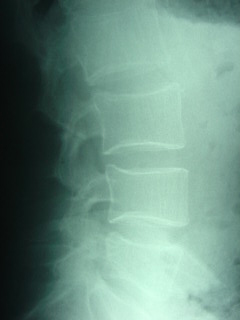

- Long periods of breastfeeding is a risk factor for the development of vertebral fractures after menopause. Because breastfeeding is so beneficial, researchers recommend adequate calcium and Vitamin D during pregnancy and breastfeeding via diet and dietary supplements as necessary. (2) Our Juneau breastfeeding mothers will want to check their diets.